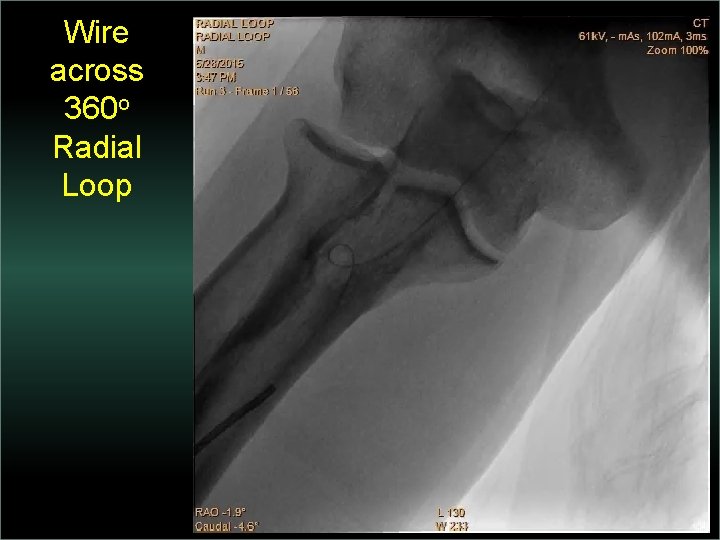

Transradial Interventions Difficult Anatomic Substrate Challenges and Solutions